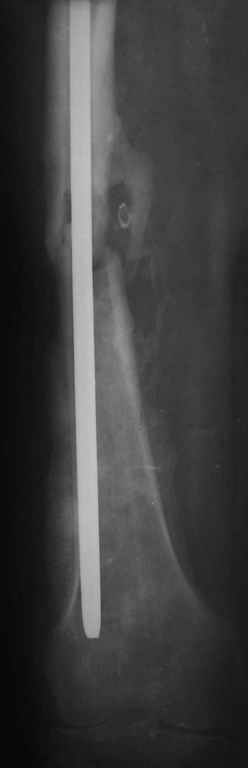

На снимке N2 виден канал от стержня во фронтальной плоскости, на уровне которого на снимке N7 уже перелом.

>“На представленных R-граммах нет снимков с АВФ. На снимке №4

>дистальный статический винт не доходит до второго кортикала “

Снимок №4 сделан после несостоятельности интрамедуллярного штифта, осложнения инфекцией канала и после миграции шурупов. Я имел ввиду, что снимок № 2 после удаления наружного фиксатора в интрамедуллярном варианте, на увеличенном снимке дырка на переднем кортексе (см. снимок) stress zone Чтобы правильно без осложнений провести half pins, необходимо соблюсти нескольких правил, во первых, они должны вводится в середине диаметра кости с предварительным просверливанием. Во время просверливания кости, сверло проходит первый, потом второй дальний кортекс и стержен вводится вручную. А иногда сверление проходит по касательной к кортексу, нагреваются местные ткани, создается ожог и локальный некроз. Или как будто делается кортикотомия с помощью сверла, как при

методе Илизарова, ослабляя кортикальный слой. Создается стрессовая зона, которая при незначительной травме может осложниться стрессовым

переломом.